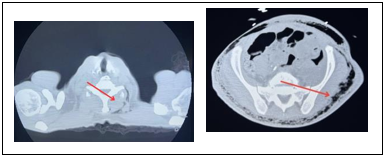

Patient was driven to an abdomen CT (Figure 1) that reported large amount of air in the abdominal wall of uncertain etiology and to a chest CT (Figure 2) that also reported large amount of air in the chest wall. After this, there was performed a CT spine lumbar (lumbar spine CT) with findings of extensive subcutaneous air with thickening of the soft tissues posteriorly for which lead in suspicious diagnosis of necrotizing fasciitis.

Figure 1 Non contrast CT chest scan axial images with no acute infiltrates, no definite mediastinal mass.

There’s large amount of air in the left sided chest wall of uncertain etiology. There’s no fracture of the rib cage. /p>

Figure 2 Non contrast CT abdomen and pelvis scan axial images with no evidence of pneumoperitoneum or ascitis.